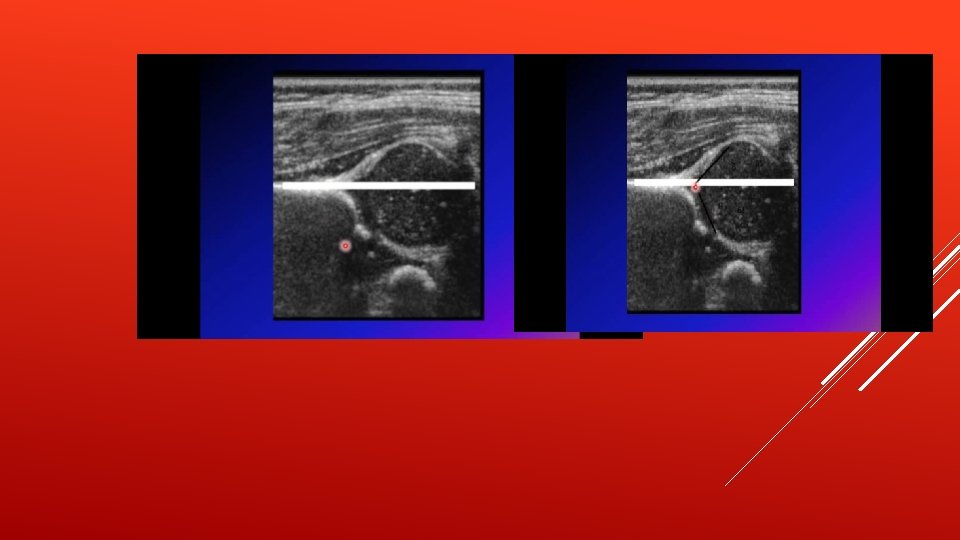

1. Barlow test : a maneuver that is performed by adducting the hip while applying light pressure on the knee, directing the force posteriorly. If the hip dislocates (pops out of socket with a ‘clunk’ is felt), the test is considered positive. The test is harmful and shouldn’t be done 2. Ortolani test : relocates the dislocation of the hip joint that has just been elicited by the Barlow maneuver by abducting the hip joint. Barlow and Ortolani tests are inapplicable after 3 months of age because of certain changes that happen in the hip joint and make it fixed and no more reducible by that age. Specifically, this tests for posterior dislocation of the hip. Affected leg will have less abduction ROM. 3. Galeazzi test “Allis sign” : It is performed by flexing the knees while lying down so that the feet touch the surface and the ankles touch the buttocks. If the knees are not level (apparent limb length discrepancy) then the test is positive. Shorter leg is the affected leg.